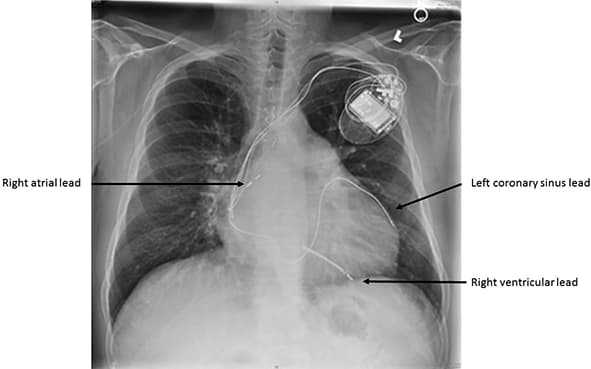

Operacija se standardno izvodi u lokalnoj anesteziji. Sam pejsmejker je generator koji proizvodi struju i ugrađuje se ispod kože. Najčešće sa leve strane, ispod leve ključne kosti, pejsmejker se stavlja u prethodno pripremljen „džep“ pod kožom. Elektrode se plasiraju kroz odgovarajuće vene, pod kontrolom rendgena, do srca, tačnije do desne komore i pretkomore, a u slučaju resinhronizacionog pejsmejkera, elektroda za stimulaciju leve komore se plasira kroz površne vene na srcu (coronarni sinus). Kada se konstatuju zadovoljavajući električni parametri, elektrode se „ušrafljuju“ u srčani mišić.